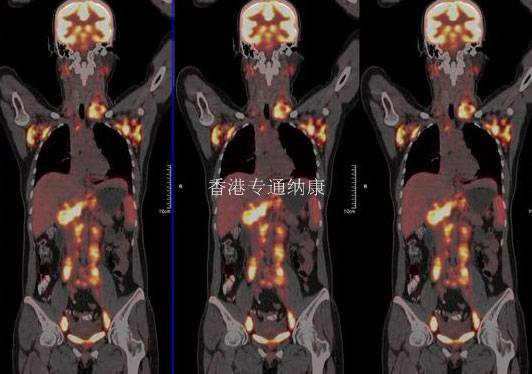

脑转移是乳腺癌患者的转移性疾病之一,尤其是HER2阳性乳腺癌患者。Enhertu是采用第一三共专有的DXdADC技术设计的抗体偶联药物,由靶向HER2的人源化单克隆抗体通过一个四肽连接子与一款拓扑异构酶1抑制剂连接而成。

这款ADC能够在抗体上连接更多的细胞毒素,从而可能具有更好的杀伤肿瘤的效果。研究报道,Enhertu在乳腺癌脑转移中具有潜在活性。